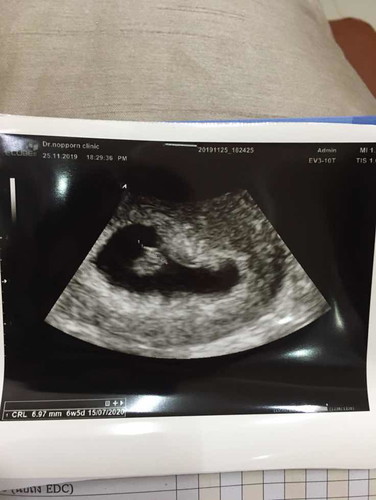

6-7 สัปดาห์หัวใจเต้นช้า ถุงไม่สวย

ท้องที่ 4 ก่อนหน้าแท้งหมด ไม่รู้ท้องนี้จะเป็นเช่นไร ท้อง 1 ท้องลม ท้อง 2 หัวใจหยุดเต้น ท้อง 3 ท้องลม ท้อง 4 (ปัจจุบัน) หัวใจลูกเต้นช้ากว่าปกติ ถุงไม่กลมไม่สวย ? ต้องประครองไปเรื่อยไปทำอะไรไม่ได้เลย แม่ท่านใด มีประสบการณ์บ้างคะ แชร์หน่อยนะคะ